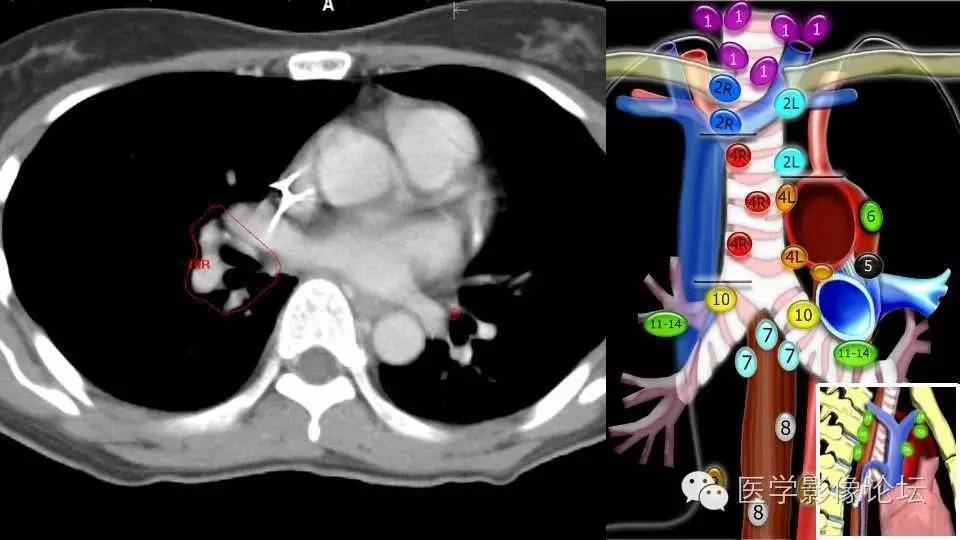

[心胸] 纵隔淋巴结分区速记

纵隔淋巴结分区速记口诀